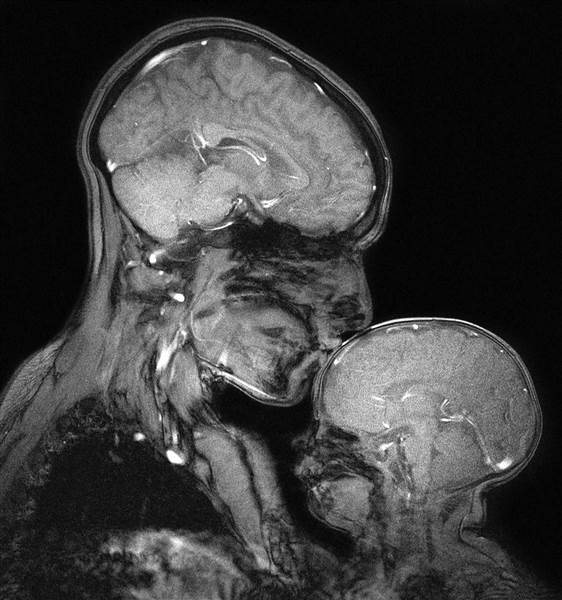

La investigadora Rebecca Saxe decidió realizarse una resonancia magnética mientras sostenía a su bebé de 2 meses, Percy, creando la primera imagen de este tipo. Ella y sus colegas lo hicieron por simple curiosas y no para algún diagnóstico o estudio en específico.

Rebecca se dedica a medir cómo la sangre de los niños fluye a su cerebro mientras les leen un cuento, así que le llamó la atención ver cómo reaccionaban ante el contacto. Los resultados fueron fascinantes: “Algunas personas lo ven y miran las principales diferencias lo delgado que es su cráneo, el pequeño espacio que existe entre su cerebro y el mundo exterior. Es tan frágil, como una pequeña caparazón”, declaró al portal Today.com.

Cabe destacar que el cerebro de su bebé no tiene mielina, un componente que aisla las fibras nerviosas. “En la otra mano, puedes ver lo similar que es al cerebro de la madre. Lo cercanas que son las medidas”, explicó la neurocientífica.

Como la resonancia tarda varios minutos, debió esperar a que su bebé se durmiera para que pudiese quedarse quieto al interior de la máquina. Pero la mezcla de arte, ciencia y maternidad hizo que el esfuerzo valiera la pena.